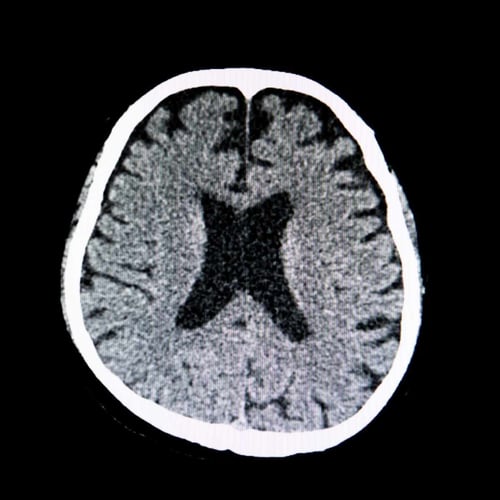

Using AI tools doesn’t make you an expert—any more than looking at your own CT scan makes you a radiologist. It just means you’re holding powerful instruments you may not fully understand.

Why Using AI Tools Doesn’t Make You an Expert (Any More Than Reading Your X‑Ray Makes You a Radiologist)

Imagine you log into your medical portal, open your MRI, zoom in and out, and carefully read the radiologist’s report. You can see the images. You can see the medical jargon. But you still don’t know how serious it is, what’s normal for your age, or what to do next. That’s the radiologist’s job, built on years of training, not a five‑minute scroll.

Owning a report is like owning imaging equipment: you still need someone who knows what they’re looking at and what to do about it.

The imaging analogy, one last time

AI in SEO is like imaging equipment in medicine:

- It’s powerful.

- It’s useful.

- It’s getting better.

But if you hand a patient their scan and say, “Good luck,” you’re not practicing medicine. You’re outsourcing outcomes to chance.

The same is true in digital marketing. If you hand your business an AI tool and call it a day, you’re hoping, not strategizing.